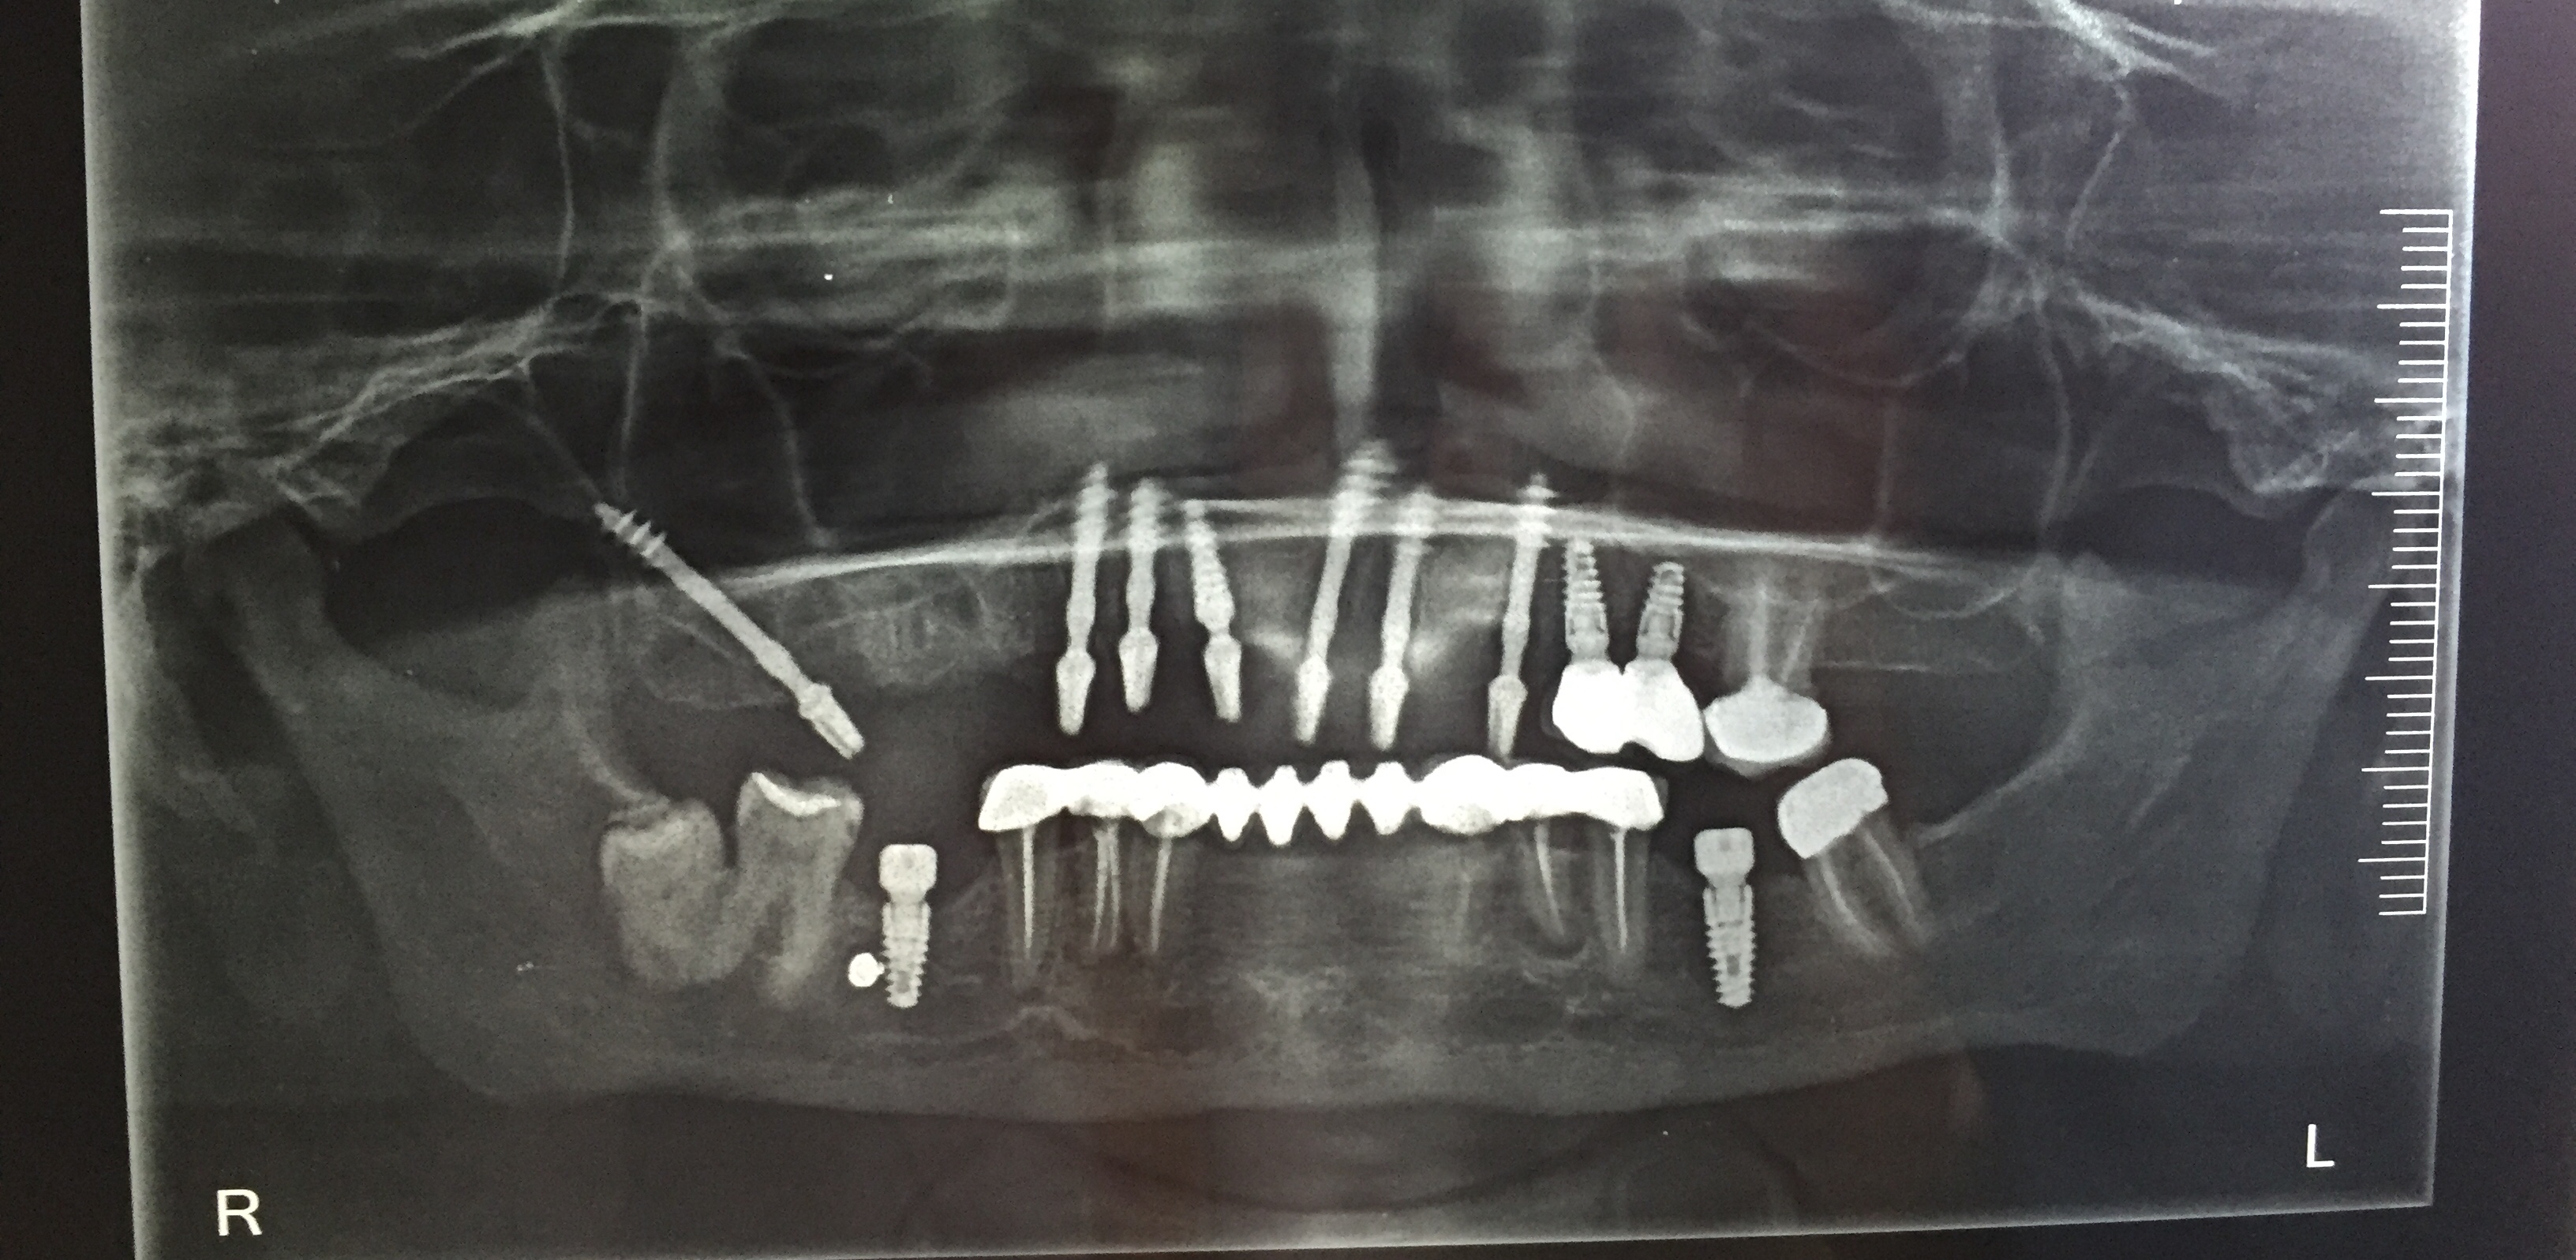

Upper Jaw Full Mouth Implants with Immediate Crowns